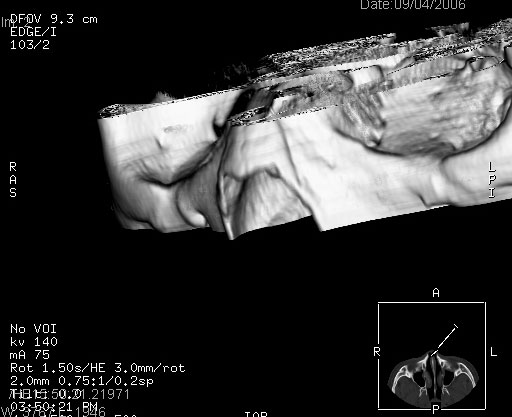

患者,男,以头面部外伤后头疼1小时为主诉入院,患者1小时前被他人打伤头部及左侧面部,眼睑无水肿,左侧面部肿胀压疼,未触及骨擦音。专科检查:耳鼻喉未见异常。

ct:平扫+冠扫:双侧鼻骨对比,冠扫s6#示右侧鼻骨尖部可见线状低密度影,边缘光滑,并见硬化.软组织未见肿胀.

诊断意见:鼻额缝(鼻骨与上颌骨额突缝),但个别同志认为是骨折.因此请同行们会诊.多谢了!